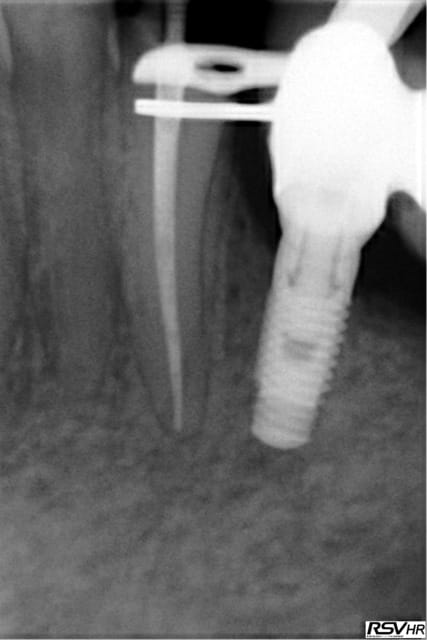

Monocone = minimum syndical vu le tarifs opposables de merde, je ne m'en cache pas, mais plus de lentulo. Des fois obturation au système B ou au mac spaden.

Apex défoncés, je ne comprend pas expliques. C'est vrai qu'il est plus simple de faire des endos à 4 mm de l'apex comme je vois souvent pour éviter de le leser je suppose.

Loin de moi l'idée de faire les meilleures endo du monde mais par contre je suis assez satisfait du résultat immédiat et à long terme, vu le minimum de temps passé à les faire (10 mn par canal en moyenne)

Tiens les endos de la semaine, que d'apex défoncés !-))

La 47 en fin le distal est obturé au système B (bouchon apical) et au mac spaden pour la partie coronaire, tu vois la différence à la radio ? Alors l'apex défoncé il faut avoir l'oeil ! peut etre mais à 25 centièmes et à conicité 6 %........-))